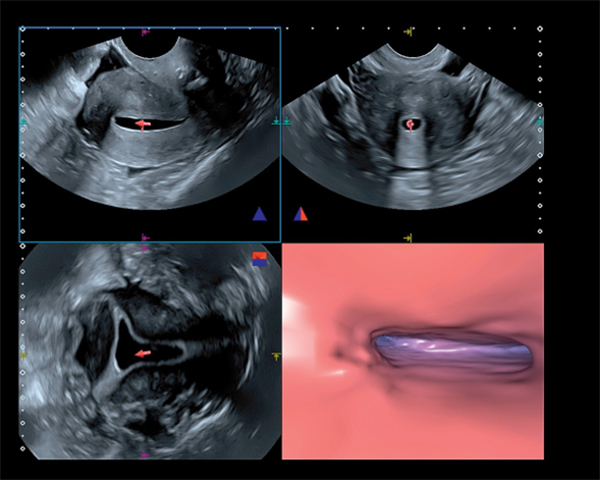

Якісна об'ємна візуалізація з високою роздільною здатністю може допомогти оцінити вагітність вже на перших етапах життя. В цьому прикладі - дихоріонічна вагітність з двійнятами на 9 тижні, де чітко визначена перегородка між обома мішками.

Режим Luminance забезпечує тривимірну реконструкцію одержуваних даних в природному вигляді з високою якістю і роздільною здатністю для максимально реалістичної візуалізації плода вже в першому триместрі.

У режимі Fly Thru можлива навігація по тривимірним об’ємним реконструйованим зображенням (порожнини, протоки і судини). Подібно віртуальній ендоскопії ця опція дозволяє досліджувати об'ємні новоутворення і планувати інтервенційні процедури.